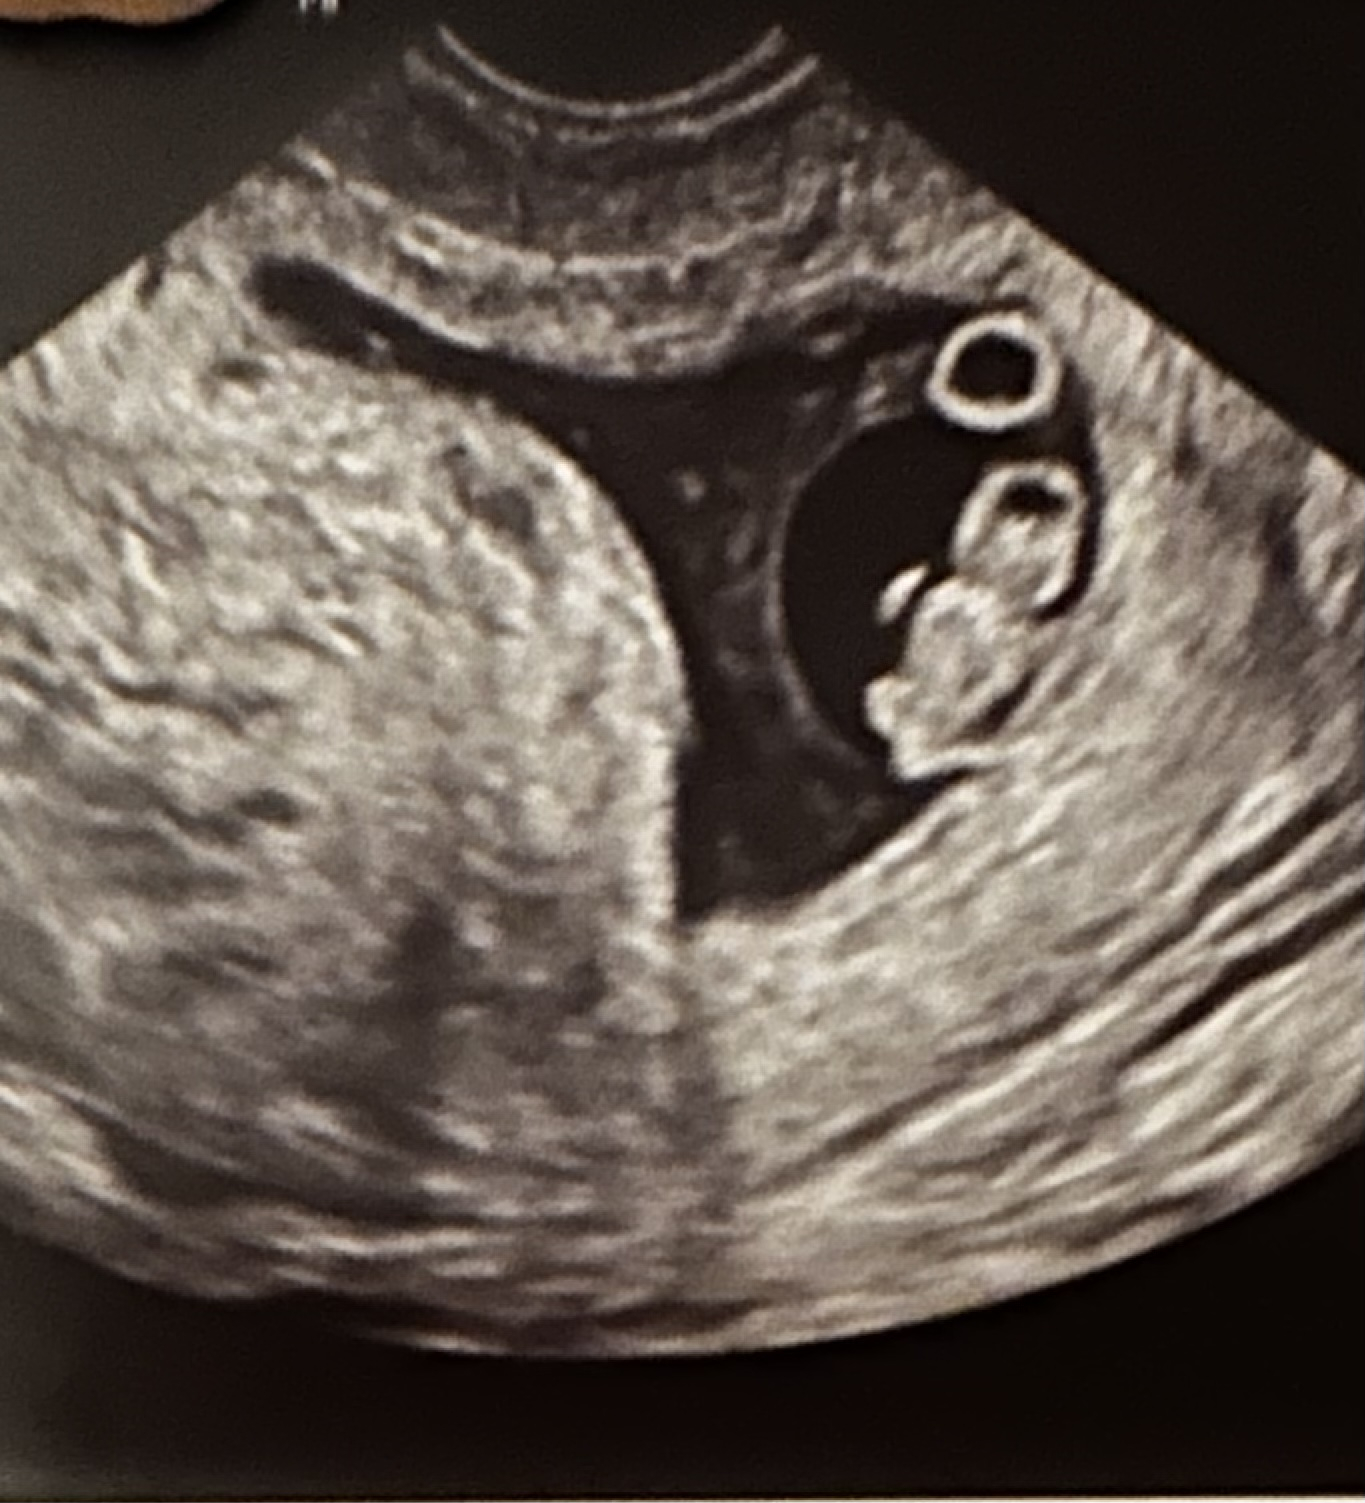

Just wanted to share two different ultrasound results in case it helps any of you. The doctor we saw for the first ultrasound came in right after and basically said we had a "slow" heartrate and could expect miscarriage. My research and instincts told me that was incorrect, and I pushed back. I had a blighted ovum last year, which was basically an empty sac at the same time (6 wks, 2 days) so seeing fetal pole and heartbeat seemed great to me! I was honestly shocked at the doctor's reaction.

The second doctor (we saw her today after the second ultrasound) told me it was irresponsible for them to flag anything over 100 at 6 weeks and that my first measurements were fine. It goes to show that there is variation among medical professionals, as well as different approaches, and on the earlier side, assuming certain elements are in place, it's ok to be optimistic!

SECOND ULTRASOUND Ultrasound date: 1/5/23 Gestational Age: 9 wks, 2 days Elements Present: Yolk sac, fetal pole, heartbeat CRL (crown rump length): 2.5cm Heart rate = 167 (per doctor, range should be 150-170) Due date = 8/8/23

For reference here are the previous ultrasound notes / measurements: Ultrasound date: 12/19/22 Gestational Age: 6 wks, 3 days Elements Present: Yolk sac, fetal pole, heartbeat CRL (crown rump length): .67 cm Heart Rate = 107 Due date = 8/10/23